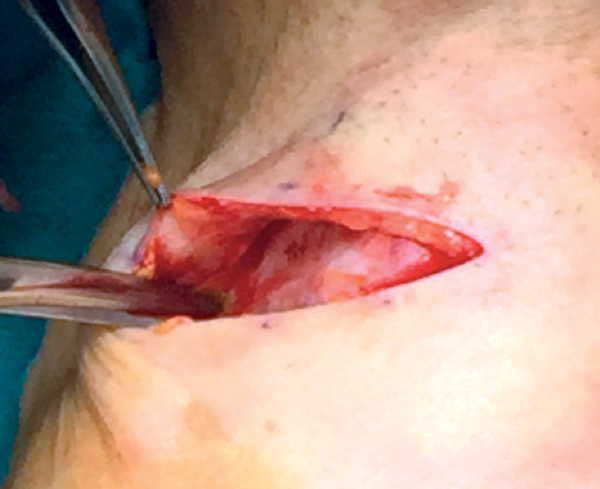

Skin incision

A transverse skin incision is made following skin crease lines; 4cm in male 3.5cm in female, halfway between the thyroid notch and cricoid (Figure 7).

Figure 7: Skin incision.